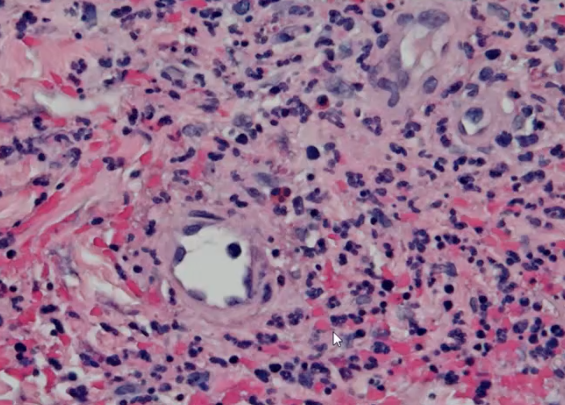

Polyarteritis nodosa

Polyarteritis Nodosa, fibrinoid necrosis

Strong evidence of fibrinoid necrosis, polyarteritis nodosa